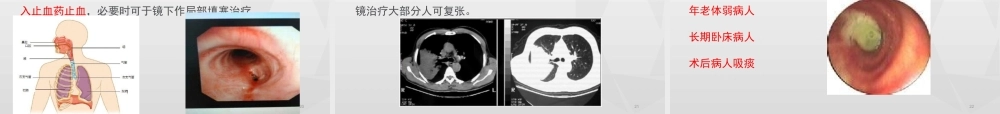

气管镜其实并不可怕青岛市市立医院东院呼吸二科郝万明1支气管镜发展简史22气管镜与胃镜4胃镜目前已作为常规查体项目气管镜可怕吗?气管镜与胃镜的区别区别气管镜胃镜手术目的咽、喉、声带、气管、支气管食道、胃、十二指肠镜子直径0.5cm(细)1cm(粗)进入方式经鼻经嘴不良反应咳嗽恶心无痛气管镜——病人可以在睡眠中完成气管镜检查。3常规支气管镜检查步骤8010203病史有无高血压病有无出血倾向等禁饮食4h以上取活动义齿,经口:牙托各项化验乙肝六项血小板计数出凝血时间心电图等抢救准备心肺复苏药物止血药物影像资料胸部X片胸部CT知情同意060504术前准备气管及支气管分支上呼吸道剖面示意图10经下鼻道进入鼻后孔会厌及声门11隆突声门下及气管12右主支气管右肺上叶支气管右肺上叶尖段支气管右肺上叶后段支气管右肺上叶前段支气管右主支气管右肺上叶尖段支气管右肺上叶支气管3气管镜能干什么14不明原因的咯血或痰中带血不明原因的局限性哮鸣音不明原因的声音嘶哑X线或CT提示肺不张、肺部块影、弥漫性病变、肺门淋巴结肿大等肺部手术前检查胸部外伤、怀疑有气管支气管裂伤或断裂机械通气时的气道管理疑有器官、支气管瘘的确诊不明原因的慢性咳嗽痰中发现癌细胞或可疑癌细胞肺或支气管感染性疾病的病因学诊断1、明确肺部肿块的性质目前影像学诊断仪器对肺部肿块的大小、部位能做出肯定诊断,但对肿块性质诊断较为困难,应用支气管镜检查,结合活检和刷片检查技术,可使肺部肿块性质诊断阳性率显著提高。162、寻找可疑和阳性痰细胞的起源痰细胞学检查发现癌细胞,而影像学检查无异常发现,这类病人在临床上称之为隐匿性肺癌,通过纤维支气管镜检查,观察支气管内的微妙异常征象,结合活检和刷检技术,能使患者早期确诊,早期治疗。荧光支气管镜——可以发现早期肺癌173、顽固性咳嗽咳嗽一般为吸烟及支气管炎、肺结核、支气管内膜结核、肺炎、异物、肺部肿瘤等疾病所致,如果发生了难以解释的咳嗽加重征象和对治疗欠佳的咳嗽,宜作纤支镜检查以明确病因。184、不明原因的喘鸣一般慢性支气管炎、支气管哮喘均可发生喘鸣,如病人无类似的病史,且喘鸣逐渐加重,此种情况多提示气管、大的支气管局部性狭窄,原因可能是气管或支气管肿瘤、结核、异物、炎症、痉挛等,应尽早行纤支镜检查以确诊。195、咯血及痰中带血咯血常见的病因有支气管扩张、肺癌。支气管内膜结核、肺结核、支气管炎、肺脓肿、肉芽肿、外伤、肺血管异常等,行纤支镜检查可查明...